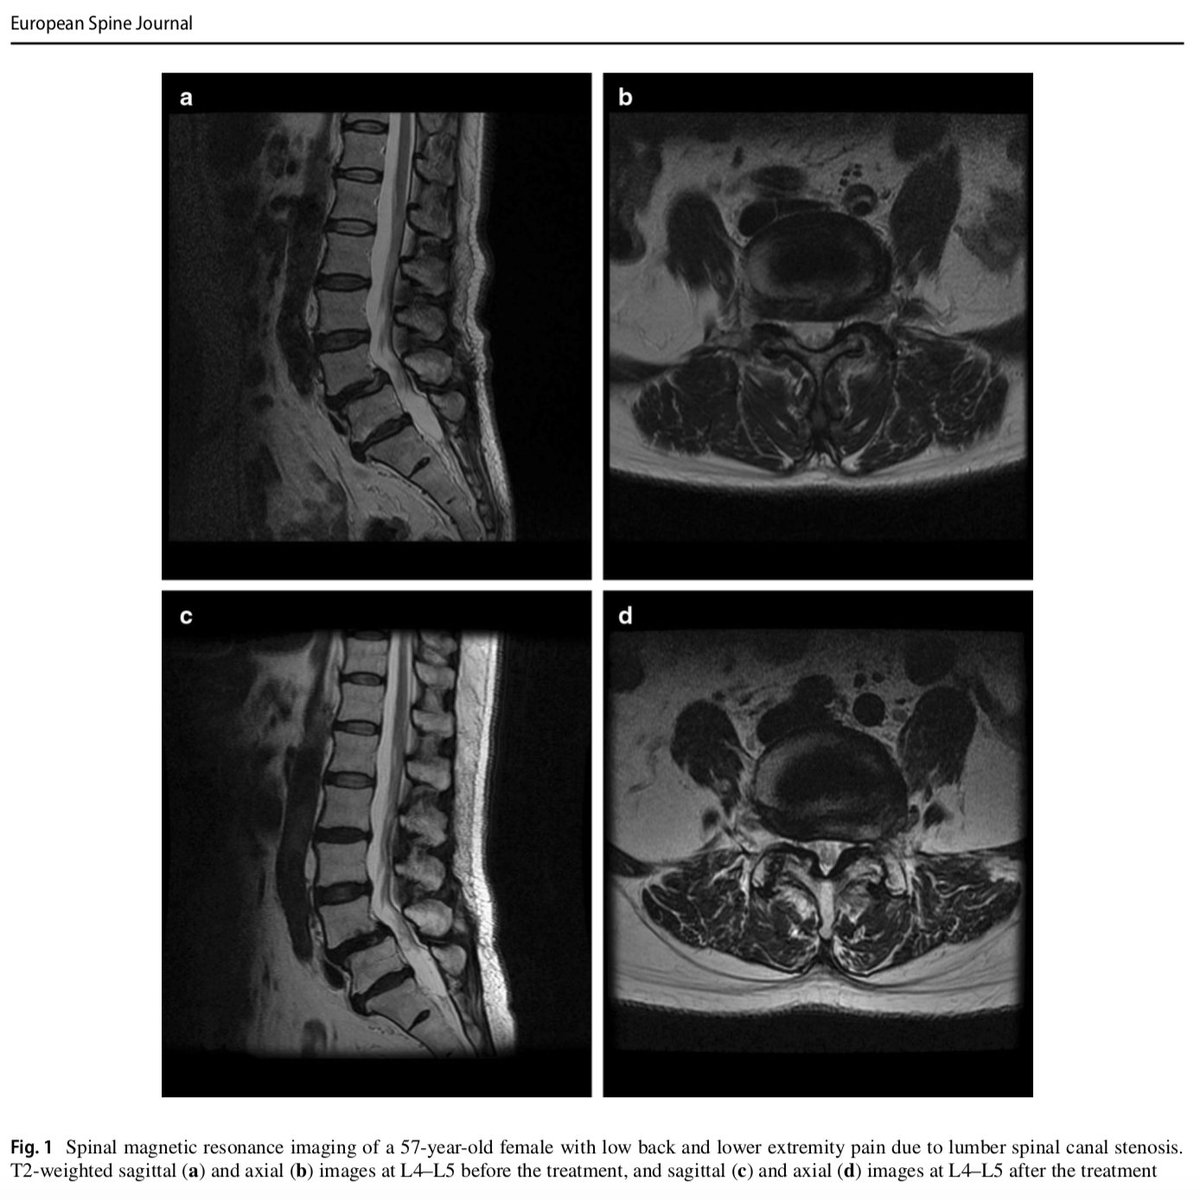

Check this article about the results of

#intrathecal injection of low-dose#bupivacaine in outpatients with chronic low back and lower extremity pain: http://goo.gl/N6bupX pic.twitter.com/oNhKy0zd7F